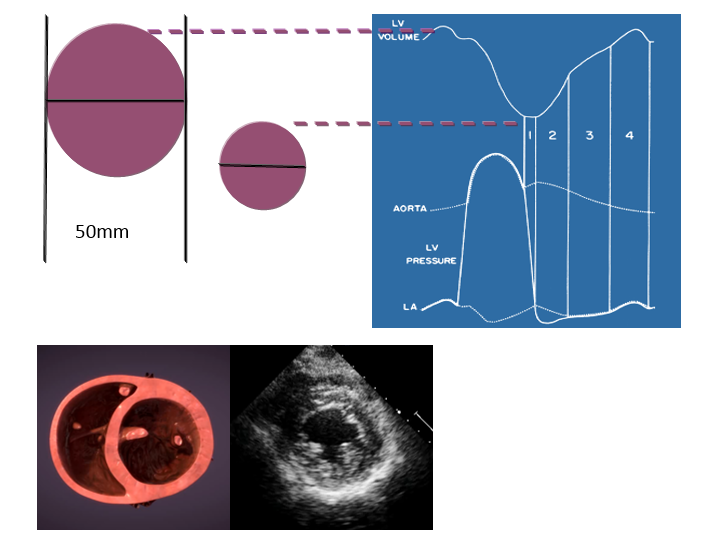

左心室有两条功能曲线(图7),容积-时间曲线和压力-时间曲线,左心室容积-时间曲线的最大值点对应着左心室舒张末容积,最小值点对应着左心室收缩末容积,最大值点和最小值点之间的差值反映每搏输出量(SV)。EF(射血分数)=SV/EDV。

图7左心室短轴切面与左心室容积/面积-时间曲线的关系

4.经胃底左心室短轴切面评价心功能

以左心室中段短轴切面为例(图7),在这个切面上,可以观察左、右心室的心腔大小,室壁厚度。左心室正常值男性55 mm,女性50 mm,正常情况下左心室和右心室横径的比例关系大约是5∶2;而左心室舒张末面积(LVEDA)和左心室收缩末面积(LVESA)的比例大致是2∶1。

TEE-Focus左心室舒缩异常的超声图像监测模式(图9,表4):

外周血管扩张模式(图9A)的特征是左房压正常,LVEDA正常,LVESA显著减小,差值增大,比值增大,室壁运动正常/增强;

心衰模式(图9B)的特征是左房压升高,LVESA与LVEDA均增大,差值减小,比值减小,室壁运动减低;

容量不足模式(图9C)的特征是左房压降低,LVESA与LVEDA均减小,差值减小,比值减小,室壁运动正常/增强。

图9经胃底左心室短轴切面用于心功能判断

表4经胃底左心室短轴切面用于左心室功能评价